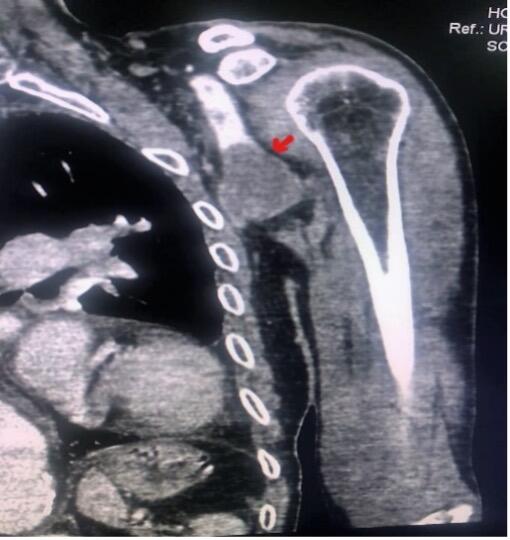

An 87-year-old man presented to the emergency department with the complaint of increasing pain and numbness in his left forearm, associated with cyanosis of the tips of the fingers of his left hand evolving since the day before (Figure 1). He had no history of trauma or vascular intervention, but he was hypertensive and receiving oral anticoagulation therapy for chronic atrial fibrillation. No axillary mass was seen in the physical examination; however, humeral, ulnar, and radial pulses were absent and a neurological examination of the upper extremity showed paresthesia of the fingers. His body temperature was within normal limits but his left upper limb was cold. Computed tomography angiography (CTA) showed a completely thrombosed fusiform aneurysm of the left axillary artery with a dimension of 4.2 cm x 2.4 cm. (Figure 2A and B). The distal arteries were not contrasted; we immediately started intravenous heparin, and urgent open surgical resection of the aneurysm was planned. Under general anesthesia and through an infraclavicular incision, we controlled the axillary artery upstream from the aneurysm, then the brachial artery after a brachial approach. The aneurysmal mass was carefully dissected and separated from the surrounding tissues. Care was taken not to injure the brachial plexus. After thrombectomy of the brachial, radial, and ulnar arteries using a Fogarty arterial embolectomy catheter (Edwards Lifesciences), we completely resected the aneurysm. Arterial continuity was established with an 8-mm ringed polytetrafluorethylene (PTFE) graft from the infraclavicular axillary artery to the proximal brachial artery, as the saphenous vein was of inadequate quality. Distal and proximal anastomosis were done in an end-to-end fashion. Distal pulses were normal after the anastomosis, and no complications occurred during the procedure. A pathological examination of the aneurysm sac revealed a true axillary artery aneurysm on an atherosclerosis basis. The postoperative course was uneventful, the patient’s symptoms improved, and he was discharged on the third postoperative day without sequelae.